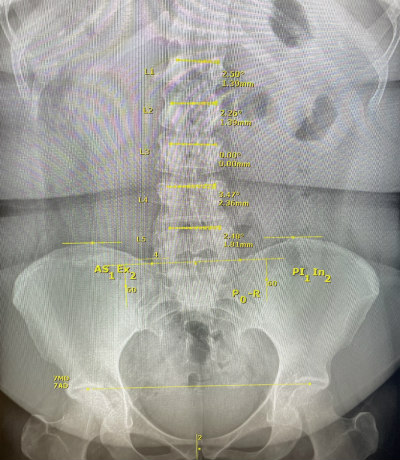

Here’s what our x-ray analysis looks like (same x-ray as above, but with lines):

Here’s an example of a “normal” x-ray.